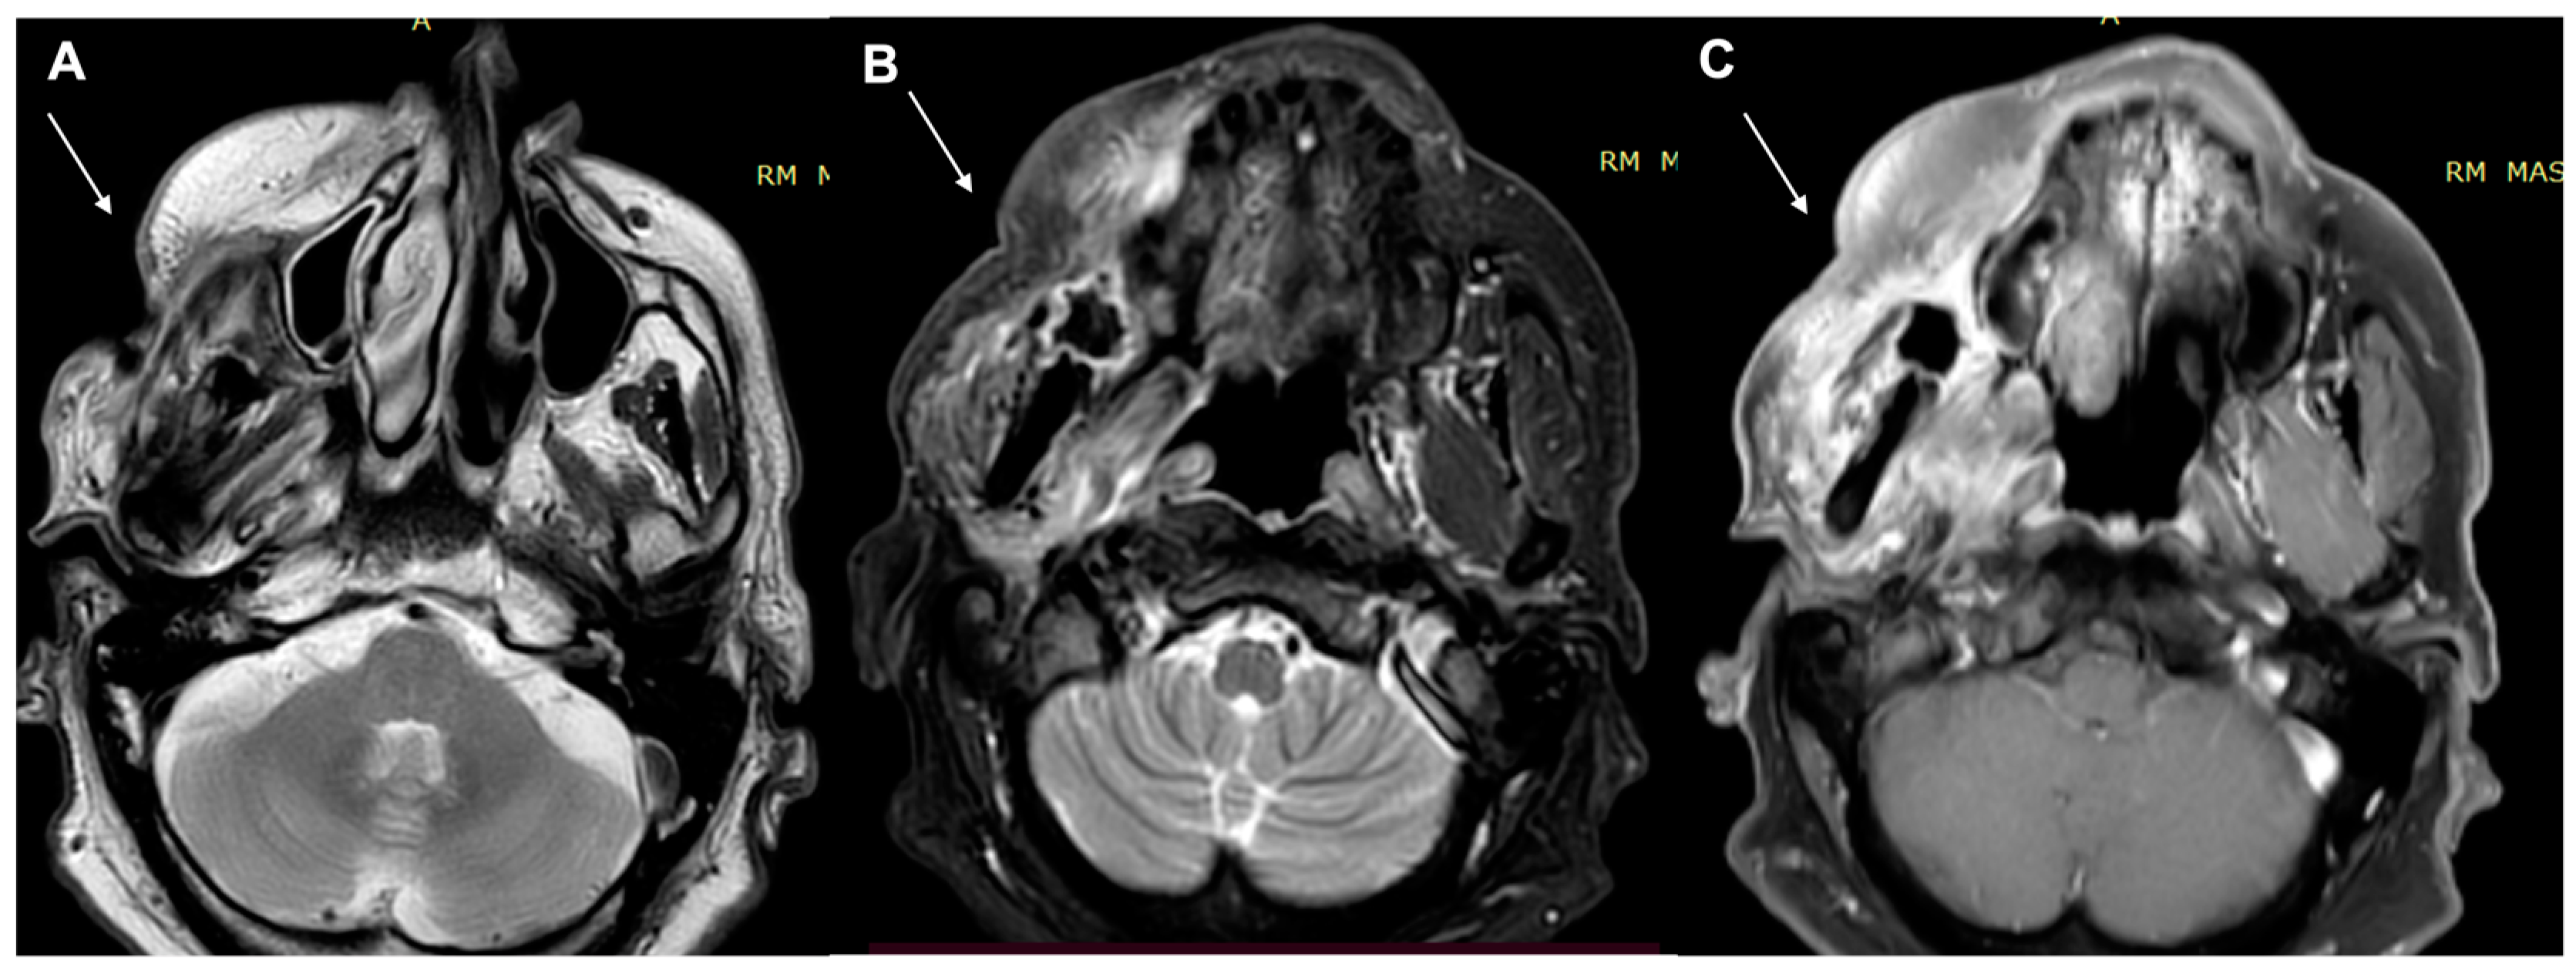

- Kawaguchi, M.; Kato, H.; Tomita, H.; Hara, A.; Suzui, N.; Miyazaki, T.; Matsuyama, K.; Seishima, M.; Matsuo, M. Magnetic Resonance Imaging Findings Differentiating Cutaneous Basal Cell Carcinoma from Squamous Cell Carcinoma in the Head and Neck Region. Korean J. Radiol. 2020, 21, 325–331. [Google Scholar] [CrossRef] [PubMed]

- Kawaguchi, M.; Kato, H.; Tomita, H.; Hara, A.; Suzui, N.; Miyazaki, T.; Matsuyama, K.; Seishima, M.; Matsuo, M. MR imaging findings for differentiating cutaneous malignant melanoma from squamous cell carcinoma. Eur. J. Radiol. 2020, 132, 109212. [Google Scholar] [CrossRef] [PubMed]

- Sheng, M.; Tang, M.; Lin, W.; Guo, L.; He, W.; Chen, W.; Li, K.; Liu, J.; Xiao, C.; Li, Y. The value of preoperative high-resolution MRI with microscopy coil for facial nonmelanoma skin cancers. Ski. Res. Technol. 2021, 27, 62–69. [Google Scholar] [CrossRef]

- Dobbs, N.; Budak, M.; White, R.; Zealley, I. MR-Eye: High-Resolution Microscopy Coil MRI for the Assessment of the Orbit and Periorbital Structures, Part 2: Clinical Applications. Am. J. Neuroradiol. 2021, 42, 1184–1189. [Google Scholar] [CrossRef]